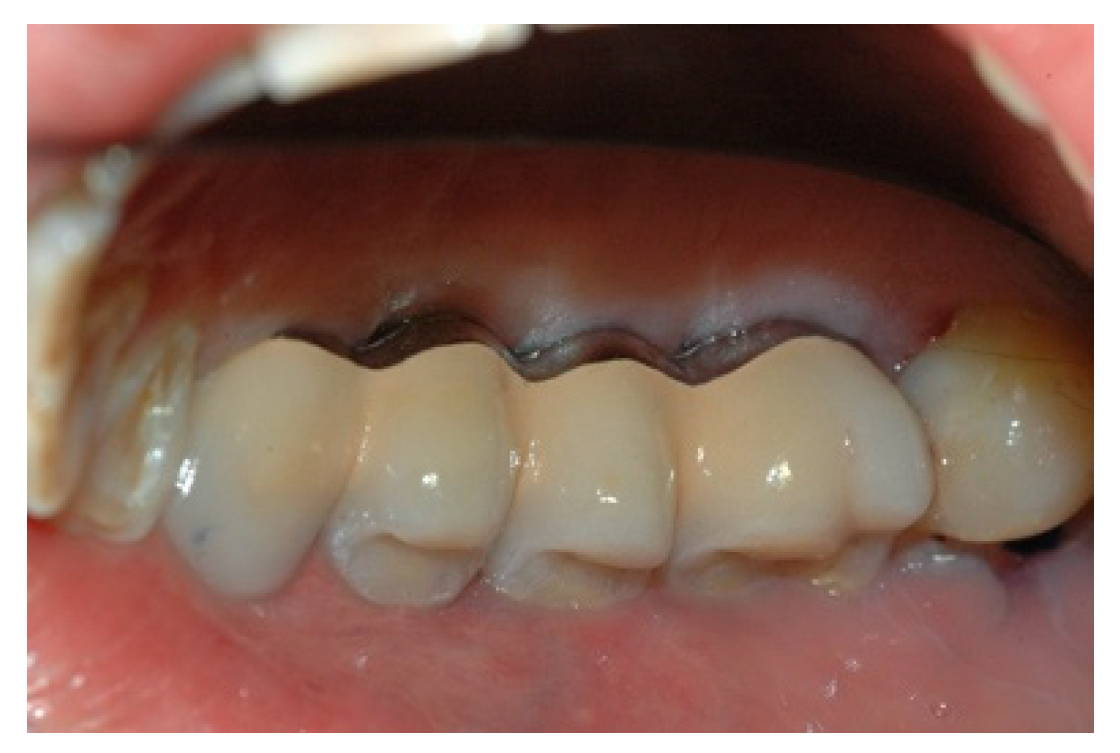

When the prosthesis was positioned, the mesostructure was fixed by tightening the screws with a torque wrench at 30 Ncm, and the superstructure was cemented by carrying out a radiographic check to evaluate the structural coherence (Figure 12, Figure 13 and Figure 14).

Figure 12. Cementing the superstructure.

Prosthesis 02 00023 g012

Figure 13. Cementing the superstructure.

Prosthesis 02 00023 g013

Figure 14. Cementing the superstructure.